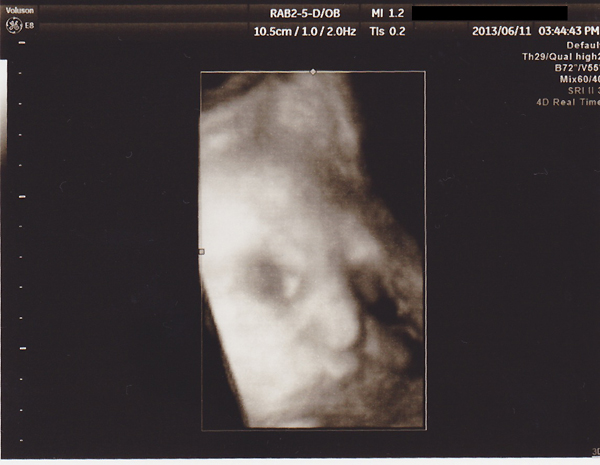

「<34w6d>検診」

2週に一度の定期検診。

赤子の発育具合は相変わらず2週程度大きめ。

前回は風邪MAXの状態で行くのしんどかったが今日は心おだやかに行ける。